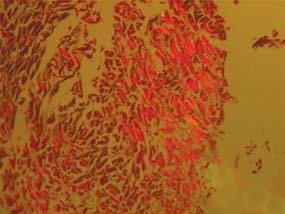

Учитывая преимущественное поражение у больного дыхательной мускулатуры, была сделана биопсия межреберных мышц, определившая наличие в мышечной ткани выраженных дегенеративных, дистрофических и атрофических изменений с участками массивных некрозов, периваскулярной лимфогистиоцитарной инфильтрации.

Учитывая возможность развития поражения мышц в рамках паранеопластического синдрома [12], был проведен онкопоиск, не выявивший искомой патологии. Несмотря на отсутствие развернутой картины ПМ, для уточнения характера поражения дыхательной мускулатуры была проведена биопсия межреберных мышц и кожи. С ее помощью были выявлены выраженные дегенеративно-дистрофические и атрофические изменения с участками массивных некрозов, лимфогистиоцитарной инфильтрацией мышечных волокон (рисунки 1, 2).

Рисунок 1. Замещение мышечной ткани на фиброзную (1) и жировую (3). Лимфогистиоцитарная инфильтрация мышечных волокон (темный цвет).

Рисунок 2. Специфическое свечение некротизированных мышц в поляризованном свете.

Полученные данные морфологического исследования позволили диагностировать ПМ с преимущественным поражением дыхательной мускулатуры, а наличие периваскулярных инфильтратов, подтверждающих воспалительный генез заболевания, исключить миопатии иного генеза (генетические, эндокринные, метастатические и др.) [13].